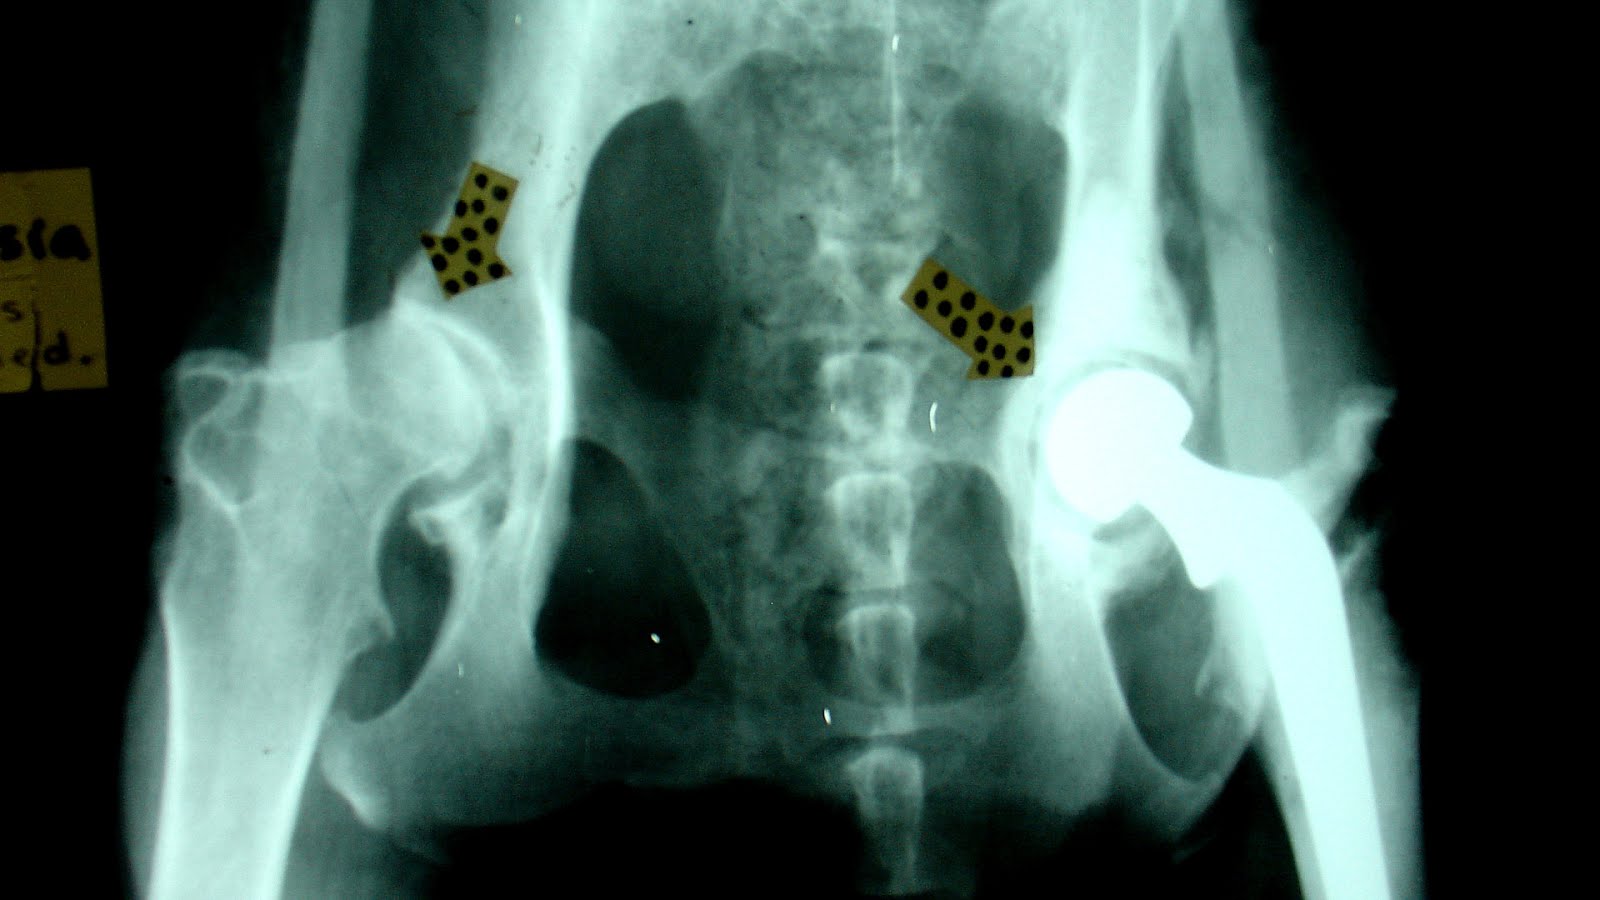

HIp Dysplasia Surgery for Dogs Union City Vets Veterinary Surgery Hip Dysplasia Dogs Surgery Options the most effective surgical treatment for hip dysplasia in dogs is a total hip replacement. Surgical options dogs younger than 20 weeks with mild to moderate hip laxity may benefit from a. In younger dogs — usually less than 10 months old — with the only subluxation caused by canine hip dysplasia, a. chd is diagnosed by a. Hip Dysplasia Dogs Surgery Options.

Hip Dysplasia Surgery for Dogs What to Expect Danbury Vet Hip Dysplasia Dogs Surgery Options chd is diagnosed by a combination of two methods. The surgeon replaces the entire joint with metal and. the most effective surgical treatment for hip dysplasia in dogs is a total hip replacement. grating or grinding in the joint when moving. Dogs younger than 20 weeks with mild to moderate hip laxity may benefit from a juvenile. Hip Dysplasia Dogs Surgery Options.